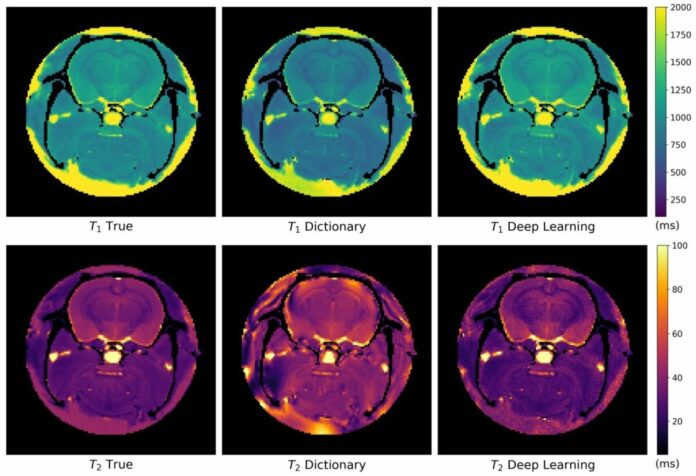

PAVIA (ITALPRESS) – E’ dall’utilizzo dell’intelligenza artificiale che arriva in Italia l’innovazione nella tecnica diagnostica della risonanza magnetica per la diagnosi e il monitoraggio delle malattie rare neuromuscolari: in pochi secondi, fino a un massimo di dieci, è possibile ottenere informazioni accurate sulle proprietà dei tessuti patologici. L’impiego sperimentale delle reti neurali per l’acquisizione delle immagini di risonanza magnetica è l’oggetto del progetto di ricerca sviluppato alla Fondazione Ircss Mondino dal trentenne Leonardo Barzaghi e dalla ventiseienne Raffaella Fiamma Cabini, dottorandi del Centro “BioData Science” della Fondazione Mondino, coordinato dalla professoressa Silvia Figini. Sono stati loro, già laureati in fisica a Pavia e Milano, a presentarlo in anteprima mondiale al CompMat Spring Workshop”, l’evento dedicato alle nuove frontiere del machine learning e della matematica computazionale, organizzato nella giornata di lunedì 22 maggio dall’Università di Pavia e svoltosi nell’aula Foscolo. Grazie a due borse di studio finanziate dal centro neurologico pavese di eccellenza, i due ricercatori hanno studiato lo sviluppo degli algoritmi di machine learning e deep learning per la previsione di biomarcatori quantitativi delle malattie dell’apparato muscolo-scheletrico. “Per supportare la diagnosi e aumentare la qualità delle immagini anatomiche ad alta risoluzione ottenute tramite la risonanza magnetica, negli ultimi anni sono state sviluppate tecniche che permettono di quantificare le proprietà fisiche dei tessuti patologici – spiega Barzaghi, attivo nell’Advanced Imaging and Artificial Intelligence Center dell’Irccs Mondino, guidato dalla professoressa Anna Pichiecchio -. L’uso dei modelli più evoluti di intelligenza artificiale consente oggi di accelerare i tempi di acquisizione delle informazioni quantitative della patologia come, ad esempio, quelle realtive alla quantità dell’infiammazione, dell’atrofia e la percentuale di grasso. Grazie alle reti neurali si possono ottenere immagini in pochi secondi, abbattendo i tempi necessari con i metodi standard, quantificabili in ore”. La ricerca di Barzaghi si è concentrata sulle immagini cliniche, mentre quella di Cabini su quelle precliniche. “Uno dei settori della nostra indagine ha riguardato la tecnica della “risonanza magnetica fingerprinting”, che consente di acquisire e calcolare in modo efficiente e più veloce, rispetto ai metodi tradizionali, mappe quantitative che rappresentano le proprietà dei tessuti. A differenza delle immagini convenzionali di risonanza magnetica, che forniscono informazioni principalmente sulla morfologia e sull’anatomia, queste nuove immagini offrono misurazioni quantitative e replicabili dei parametri specifici dei tessuti”. Il vantaggio principale di questa tecnica – sottolinea la ricercatrice, attiva nell’International Center for Advanced Computing in Medicine dell’Università di Pavia, guidato dal professor Alessandro Lascialfari – “è la riduzione dei tempi di acquisizione, così da migliorare il comfort del paziente durante l’esame di risonanza magnetica e apportare vantaggi economici alle strutture sanitarie, sia in termini di risparmio energetico per il funzionamento delle macchine sia per la possibilità di analizzare più pazienti”. “Fin dalla sua nascita avvenuta nel 2017, il Centro “BioData Science” – commenta la responsabile scientifica, Silvia Figini, direttrice del dipartimento di Scienze politiche e sociali dell’ateneo – ha indirizzato la sua attività di ricerca nello sviluppo di algoritmi per l’analisi automatica di immagini biomediche sia in ambito clinico che preclinico. I risultati ottenuti da Barzaghi e Cabini incoraggiano l’ulteriore applicazione delle tecniche di machine learning, deep learning e modellistica matematica in ambito clinico, offrendo nuove opportunità di ricerca. Proseguiremo il lavoro che abbiamo iniziato, sviluppando metodi innovativi che consentano di velocizzare, aiutare e migliorare la valutazione delle analisi mediche”.(ITALPRESS).